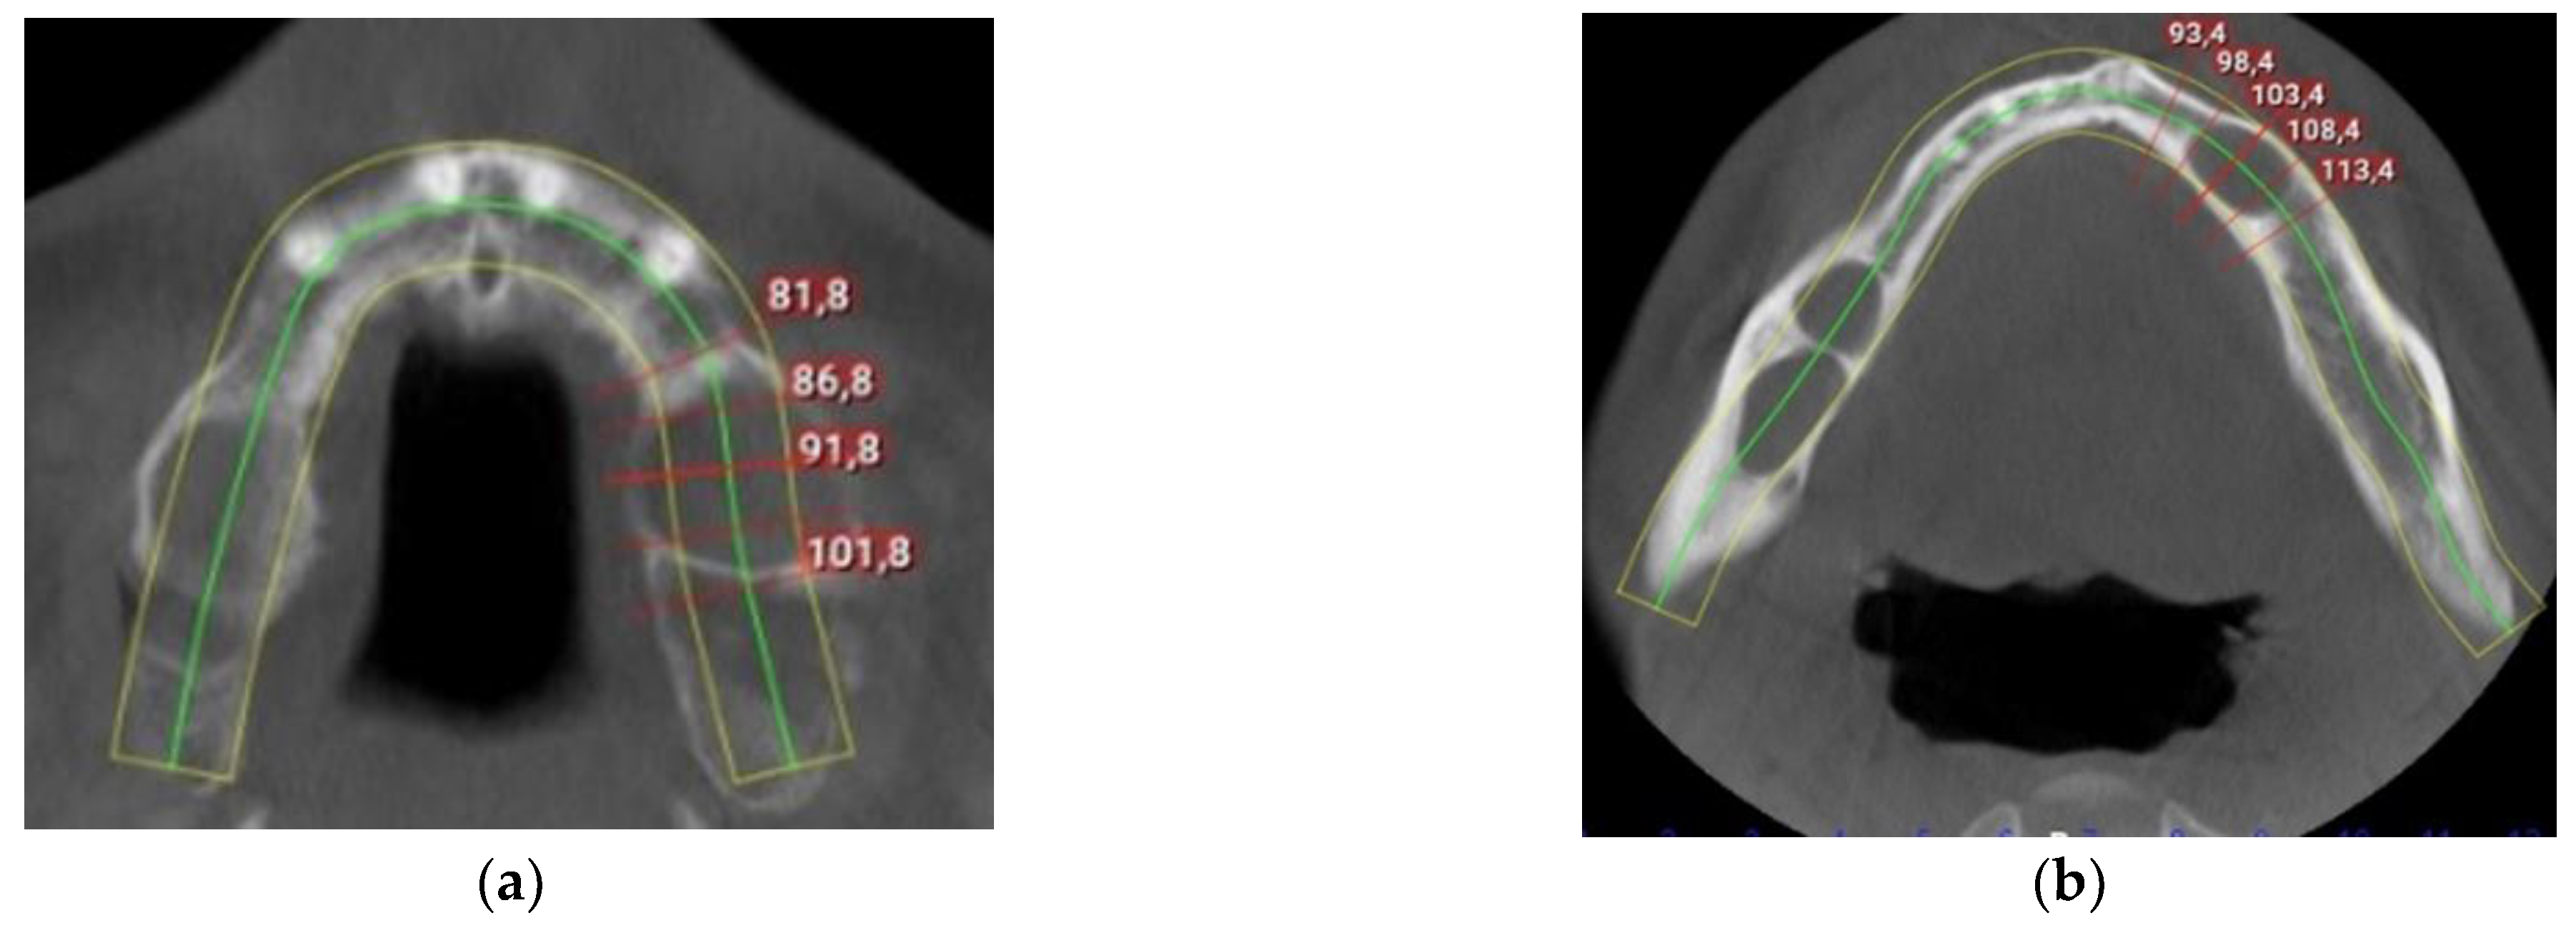

2. Detailed Case Description

3. Results